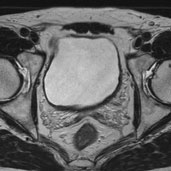

図2

図3

54 歳男性で1 年前から血尿あるも放置してい た。図2 は治療前のMRI で膀胱左側に基部の広 い大きな非乳頭状腫瘍で表面石灰化していた。 Complete TUR 後に動注療法34 回、2 年間施 行する。図3 は治療後のMRI で再発なく、遠隔 転移も認めない。治療開始後4 年目である。